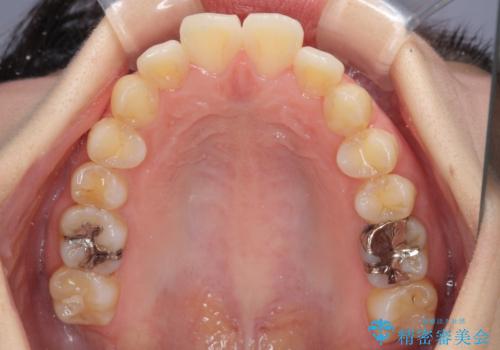

- 口元の突出感と口の閉じにくさを気にして来院された患者様です。

上下左右第一小臼歯4本を抜歯し、ワイヤー装置にて口元を引っ込めるよう矯正治療を行うこととしました。

ご友人などがびっくりするほど口元の突出感を改善することができ、患者様には大変満足していただきました。